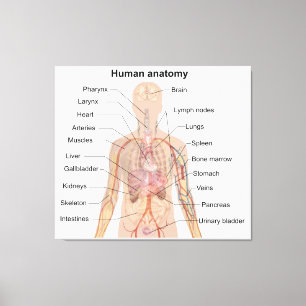

Anatomi i mänskliga organ vykort

Pris23,00 kr

Anatomi i mänskliga organ poster

Pris229,00 kr

Anatomi i mänskliga organ canvastryck

Pris1 425,00 kr

Anatomi i mänskliga organ hälsningskort

Försäljningspris 49,00 kr. Ursprungligt pris 54,00 kr.